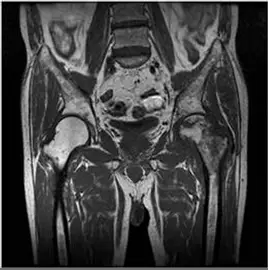

- 磁振造影 MRI (T1-weighted image, T1WI):

- 這是診斷 AVN 的黃金標準影像。

- 左側股骨頭 (圖片右側):在股骨頭上方可見一條明顯的低訊號蜿蜒帶 (serpentine low signal intensity band)。這條黑色的線是壞死骨與存活骨交界的硬化邊緣 (sclerotic rim),為 AVN 的病理特徵性表現。

- 該線條上方的股骨頭區域訊號不均,顯示骨髓水腫或壞死變化。

- 右側股骨頭 (圖片左側):呈現均勻的高訊號 (脂肪訊號),為正常表現。

- 影像符合:MRI T1WI 上的 "Serpentine line" (蜿蜒線) 或壞死區域的邊界線是 AVN 的典型特徵。X光顯示關節間隙相對保留,排除了原發性關節炎。

患者為中年男性,具備長期酗酒的高風險因子,臨床表現為單側髖部疼痛。MRI T1WI 影像清楚顯示左側股骨頭內有典型的低訊號蜿蜒帶 (serpentine line),界定了壞死區域,這是 Avascular Necrosis (AVN) 的確診性特徵。相比之下,OA 會有關節間隙狹窄,骨肉瘤會有侵襲性骨破壞,嗜伊紅性肉芽腫則好發於兒童且呈溶骨性變化。因此,最可能的診斷為 (A)。

- T1WI:低訊號蜿蜒帶 (Serpentine low signal band)。

- T2WI:雙線徵 (Double line sign) — 內圈高訊號 (肉芽組織) 包裹外圈低訊號 (硬化骨)。